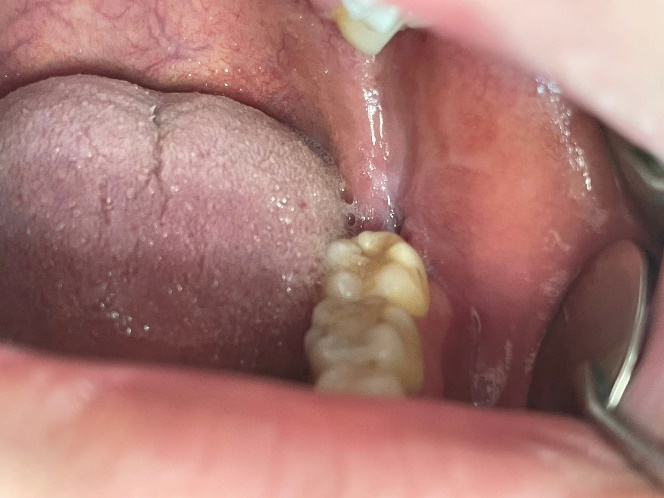

Răng khôn hàm dưới bên trái sau khi được phẫu thuật